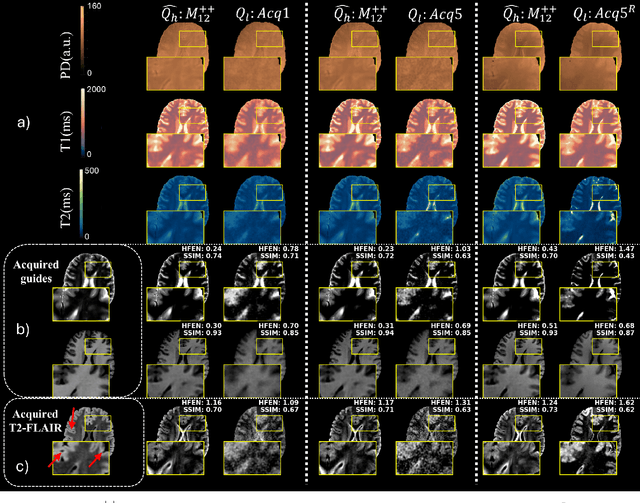

Abstract:Quantitative MRI (qMRI) offers significant advantages over weighted images by providing objective parameters related to tissue properties. Deep learning-based methods have demonstrated effectiveness in estimating quantitative maps from series of weighted images. In this study, we present qMRI Diffusor, a novel approach to qMRI utilising deep generative models. Specifically, we implemented denoising diffusion probabilistic models (DDPM) for T1 quantification in the brain, framing the estimation of quantitative maps as a conditional generation task. The proposed method is compared with the residual neural network (ResNet) and the recurrent inference machine (RIM) on both phantom and in vivo data. The results indicate that our method achieves improved accuracy and precision in parameter estimation, along with superior visual performance. Moreover, our method inherently incorporates stochasticity, enabling straightforward quantification of uncertainty. Hence, the proposed method holds significant promise for quantitative MR mapping.